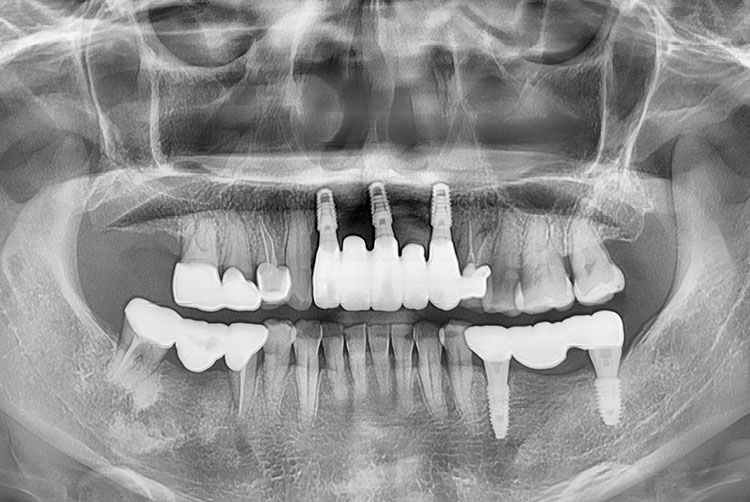

PX20230712_093703_5281_85105753.jpg

치료후 : 2023-07-12

세종치과는 많은 환자와 다양한 케이스를 바탕으로 항상 편안한 임플란트 수술을 제공하고자 노력하고,

오래동안 튼튼히 쓸 수 있는 임플란트 수술을 가장 큰 목표로 삼고 있습니다.